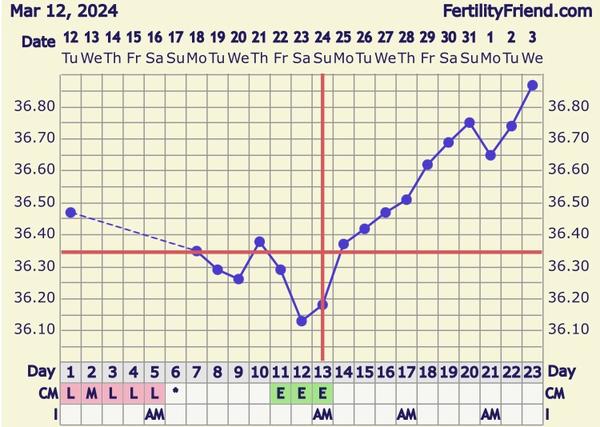

@majoralka graf máš krásny! 😍 ja by som už určite nevydržala 😂

@majoralka no teplotu máš krásnu 🥹nech sú tam zajtra //

@zanzilady áno, teplota je krásna, ale uvidíme aká bude ráno a podľa tej skúsim test 😊 ty ideš testovať až piatok?

Mám v pláne zajtra alebo piatok, tak asi skúsim zajtra ráno podľa teploty 😊